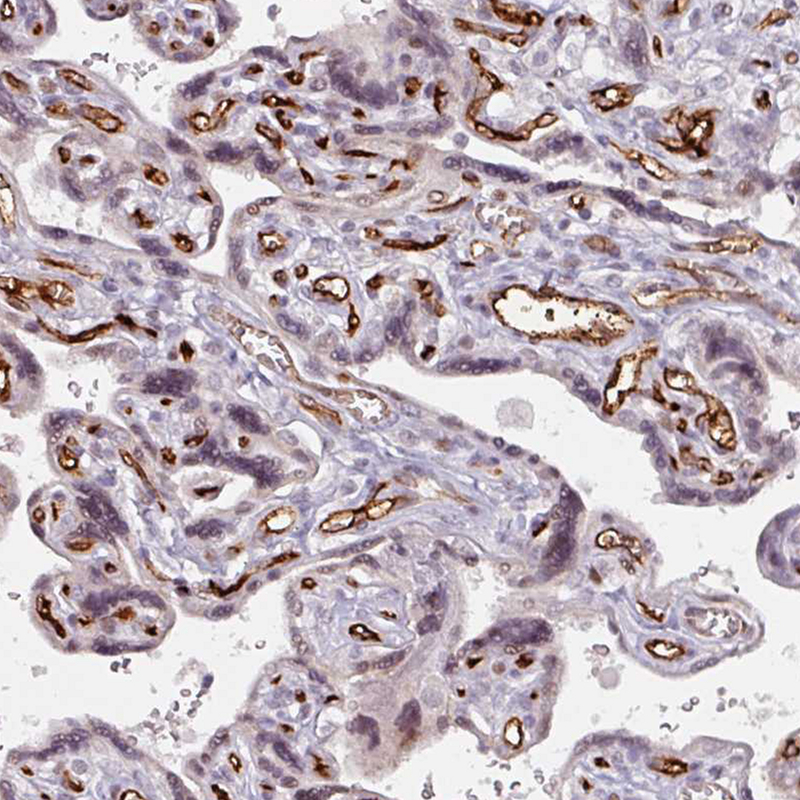

Immunohistochemistry analysis in human placenta and cerebral cortex tissues using HPA036723 antibody. Corresponding CD34 RNA-seq data are presented for the same tissues.